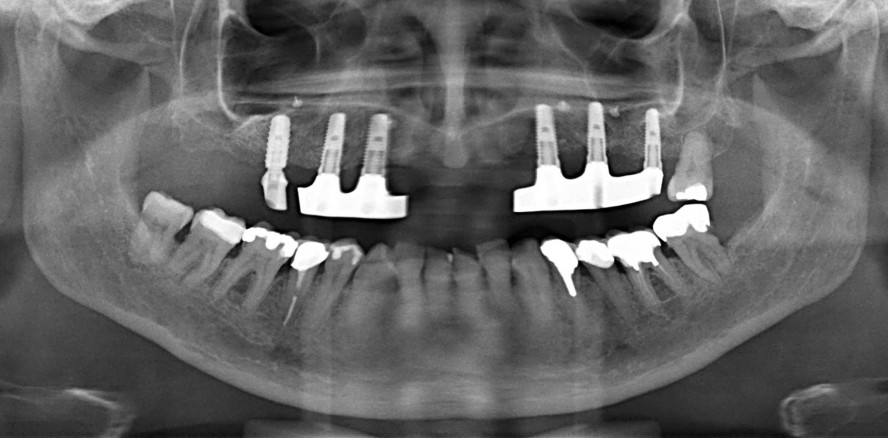

Im August 2019 stellte sich die damals 68-jährige Patientin mit einem „maximal gebrauchten“ Gebisszustand vor. Sie kam in die Praxis, um sich eine zweite Meinung einzuholen sowie mit der Bitte einer möglichen Behandlungsübernahme. Im Oberkiefer der Patientin waren noch zehn eigene Zähne vorhanden, im Unterkiefer 13. Ein Zahnersatz war nicht vorhanden. Das Kauorgan litt größtenteils unter massiven parodontalen Schäden. Die Zähne 13, 23, 24, 27 im Oberkiefer sowie 44, 43, 33, 34, 35, 36, 37 sollten in die definitive Planung einbezogen werden. Der Kieferhöhlenboden war weit ausgeprägt, was implantatchirurgisch Beachtung finden muss (Abb. 1 und 2). Die Patientin war in einem guten allgemeinen Gesundheitszustand, auch komplizierteren Behandlungsschritten aufgeschlossen und wollte nach ausführlichen Beratung an einem definitiv festsitzenden Behandlungsziel festhalten.